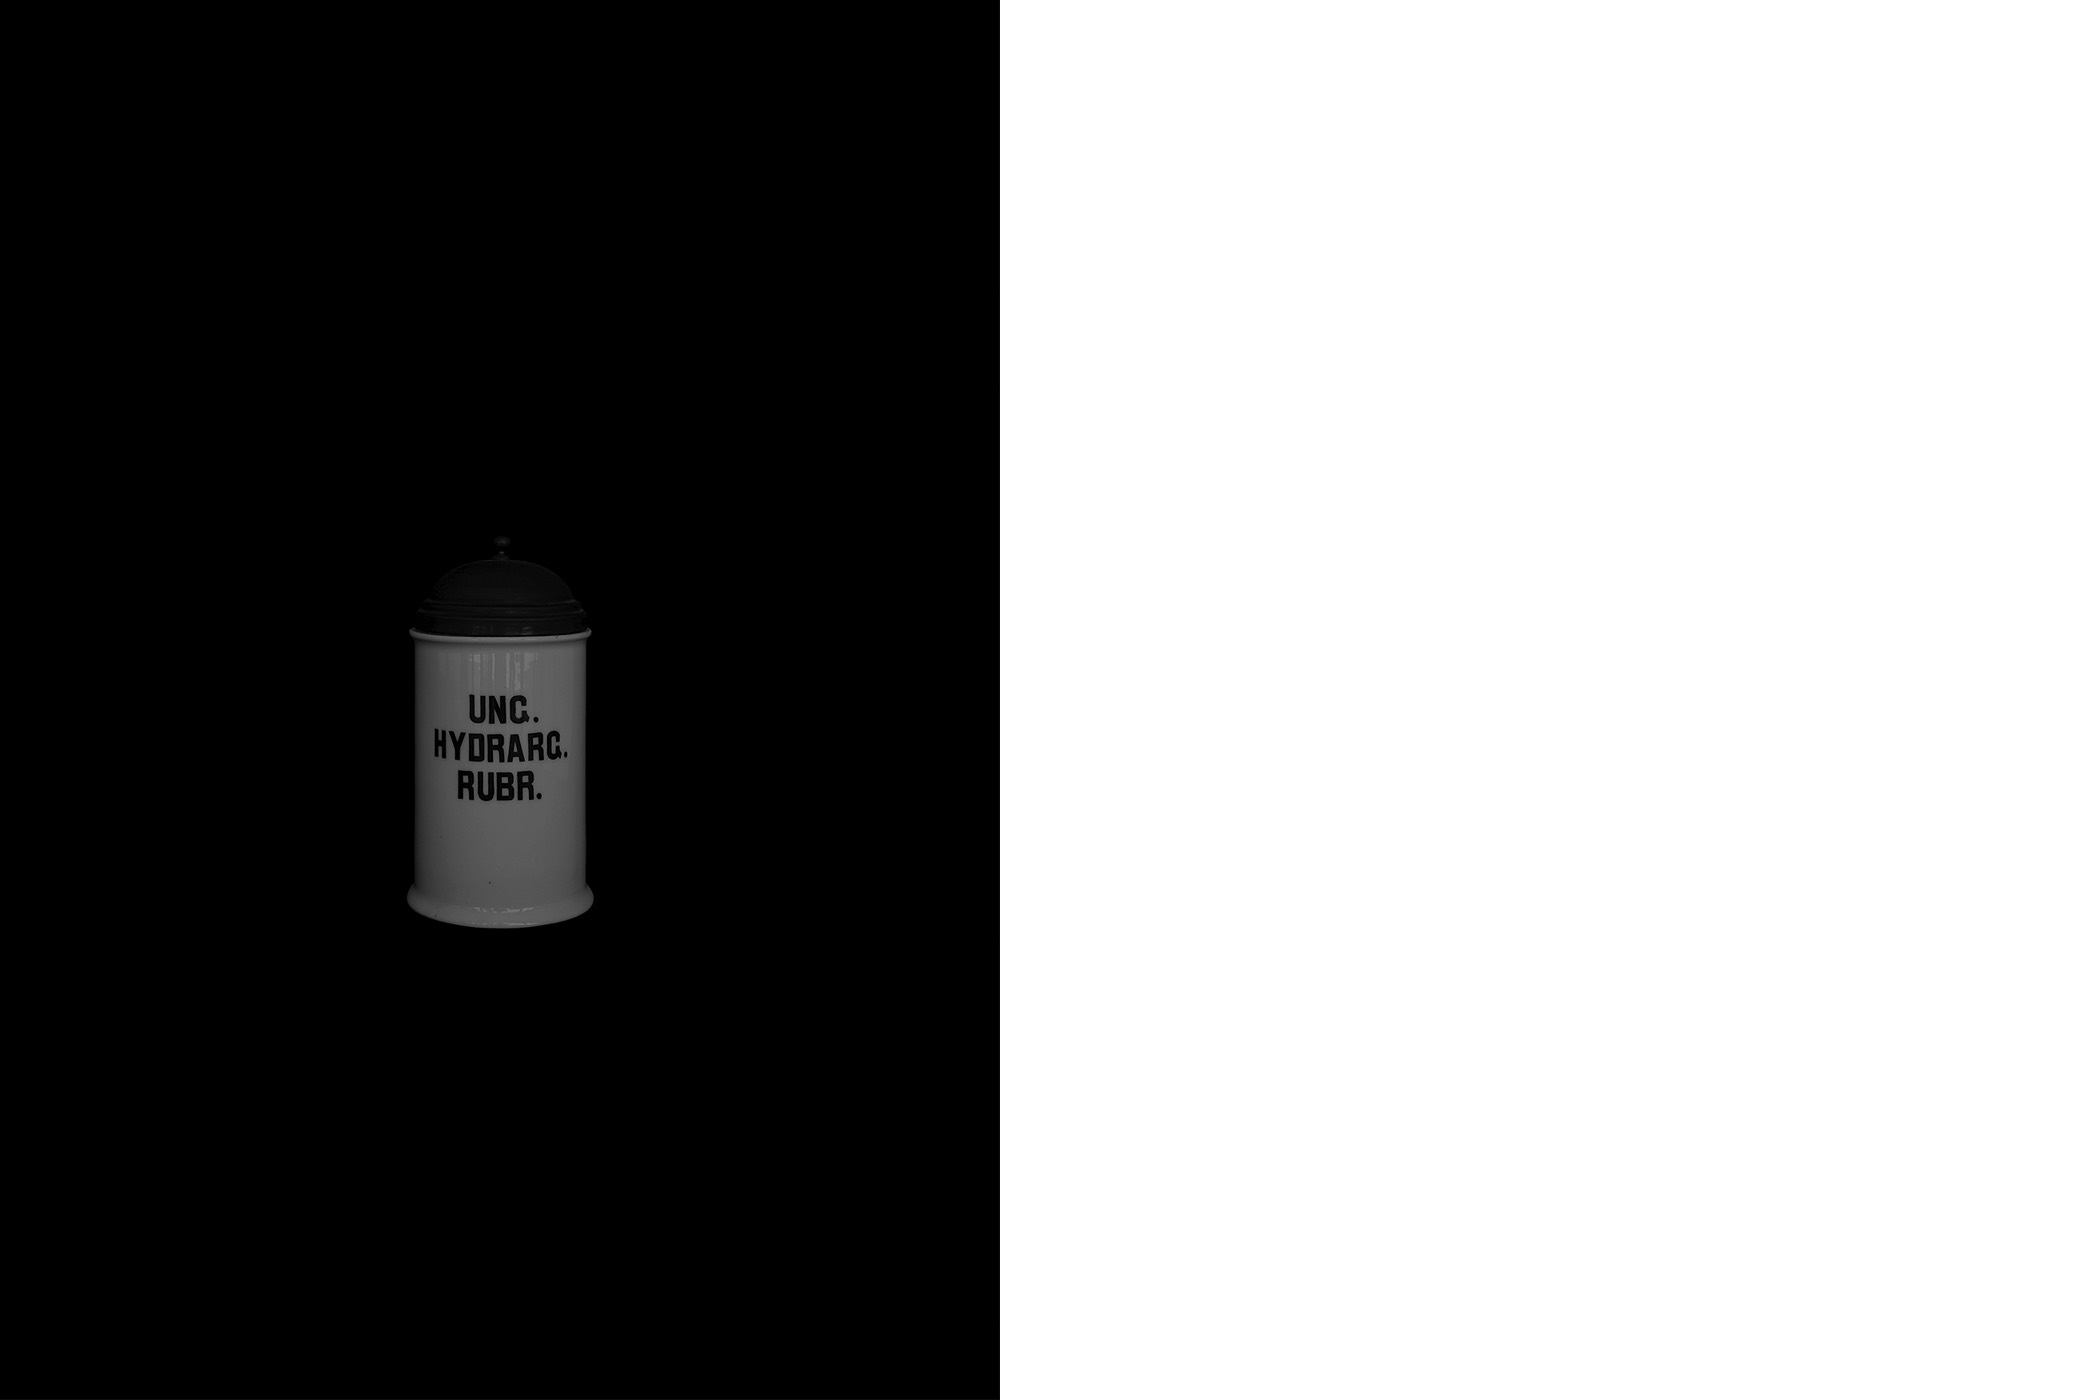

The first series draws from the collection of the Historical and Maritime Museum of Istria, featuring photographs of ceramic and glass apothecary jars transferred onto black paper using silkscreen printing. Instead of traditional ink, the prints were made with powdered active pharmaceutical substances, resulting in faint, almost ghostly images that echo the fragility and ephemerality of the source material.

The first series draws from the collection of the Historical and Maritime Museum of Istria, featuring photographs of ceramic and glass apothecary jars transferred onto black paper using silkscreen printing. Instead of traditional ink, the prints were made with powdered active pharmaceutical substances, resulting in faint, almost ghostly images that echo the fragility and ephemerality of the source material.

Untitled (Archive Pharmacy), 2024

screen printing on paper with color obtained from the powder of the active substances of medicines

graphic sheet 70 x 50 cm, framed 70,5 x 50,5 x 3,5 cm

1-20

Untitled (Archive Pharmacy), 2024

screen printing on paper with color obtained from the powder of the active substances of medicines

graphic sheet 70 x 50 cm, framed 70,5 x 50,5 x 3,5 cm